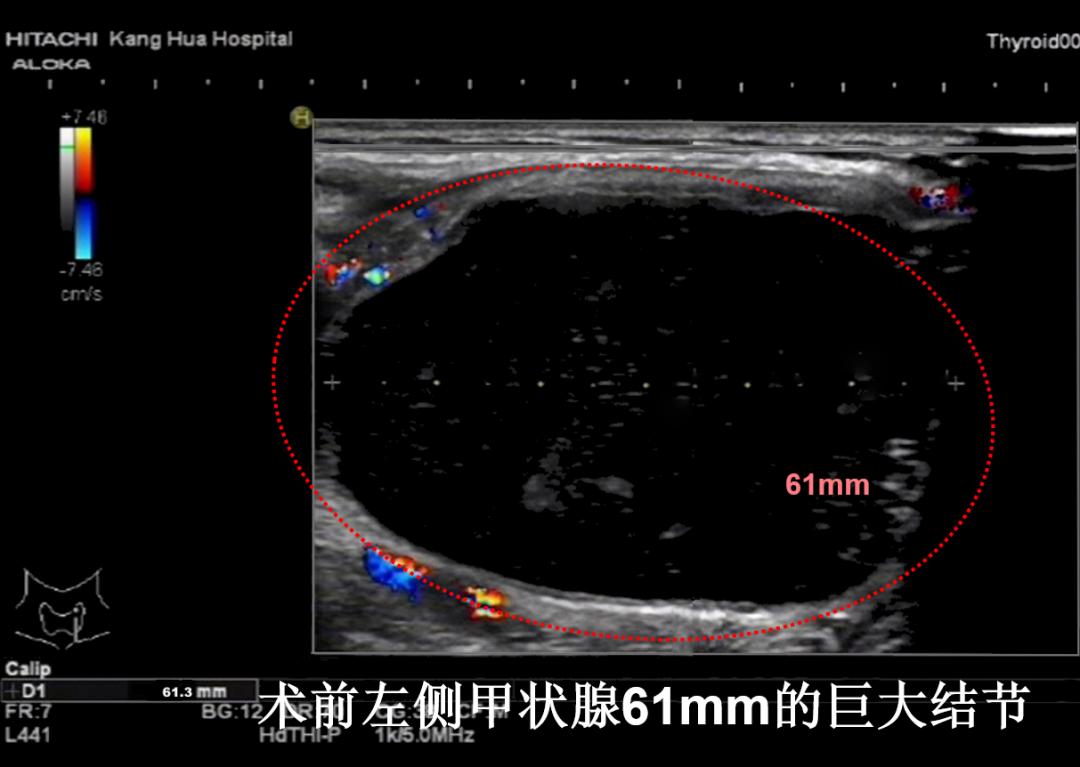

病例②:左侧颈部6cm巨大甲状腺结节,经微创消融后,肿物完全消失,颈部恢复正常外观

微创消融前后超声对比,体积缩小99%